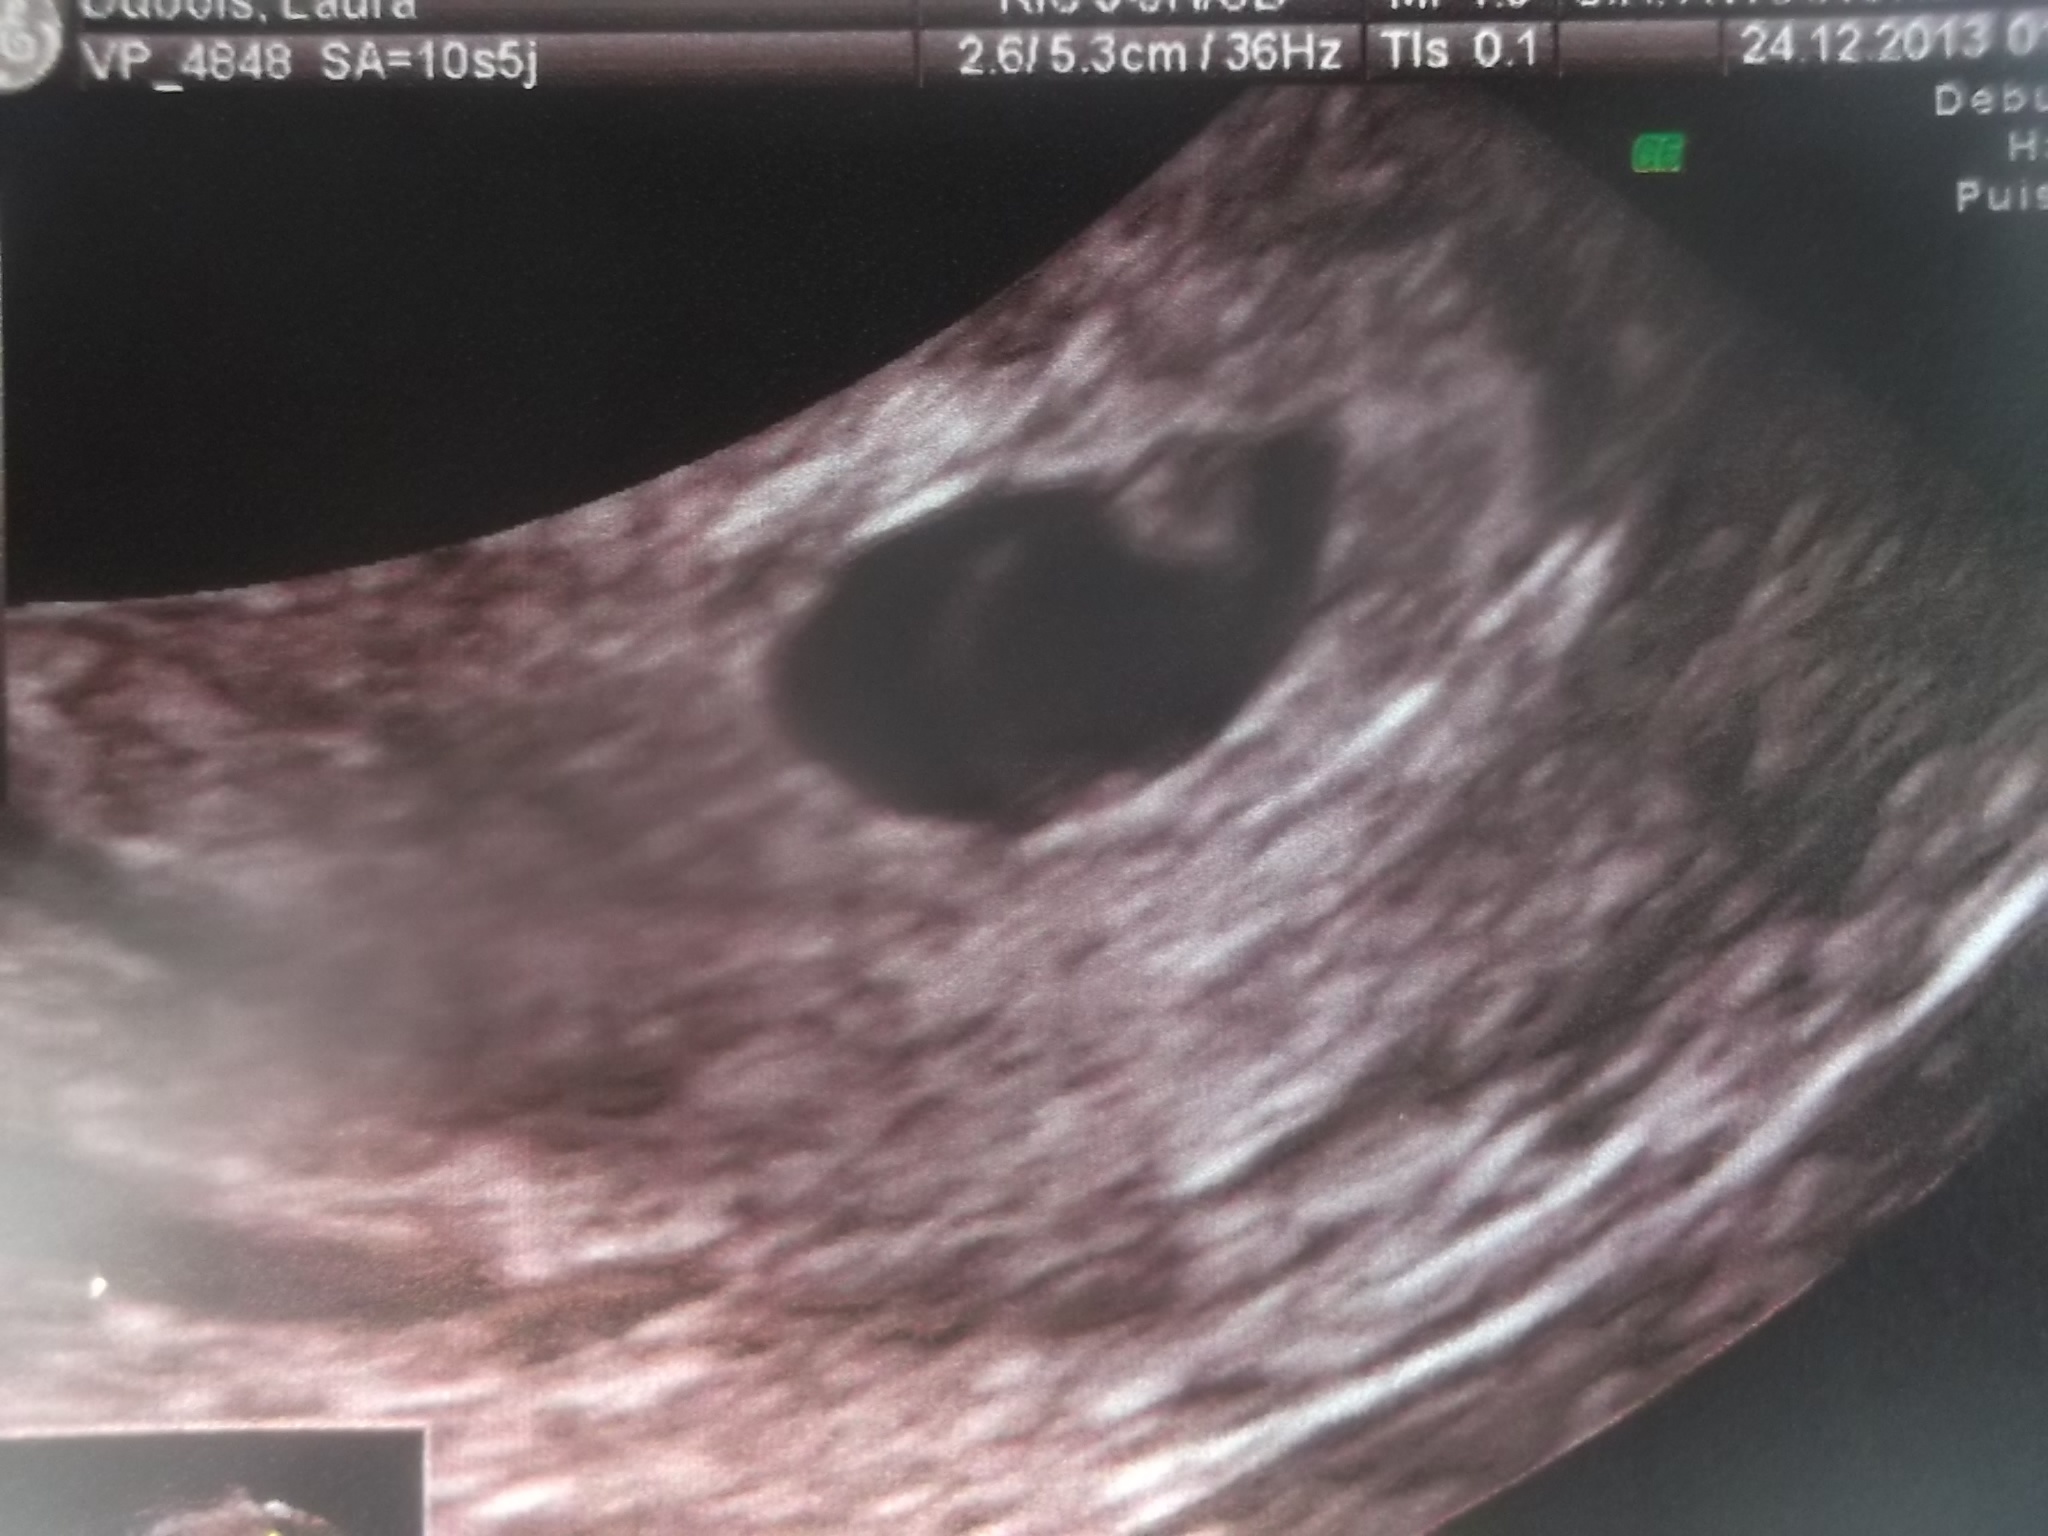

voila se que je peut te montrer et apparemnt je sui a 6sa

c'est le sac de grossesse qui mesure 12.9 mm et ce qui est dedant 2.5 mm